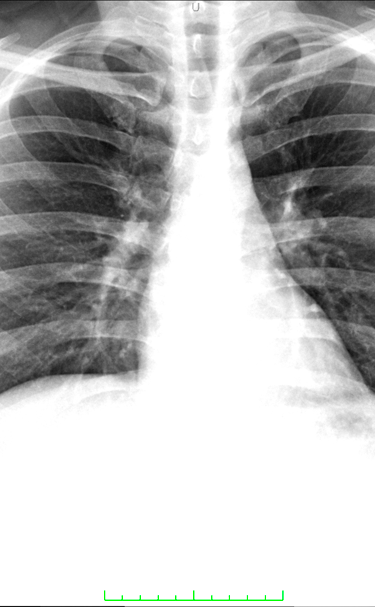

Radiología digital de alta calidad y precisión.

RADIOLOGIA GENERAL DIGITAL

Radiología Digital y Mamografia

Contamos con tecnología avanzada para diagnósticos precisos y confiables en radiología digital.

Galería Médica

Explora nuestros servicios de radiología y medicina regenerativa.